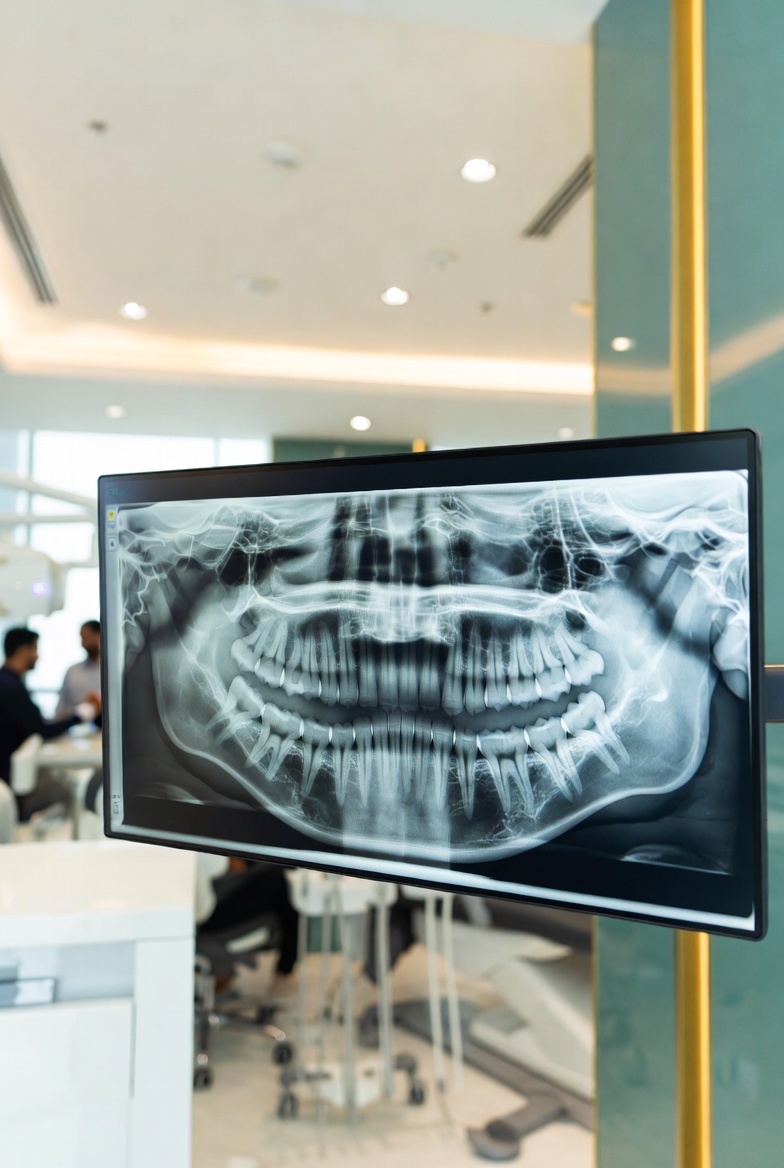

Our digital dental X-rays Dubai technology produces high-resolution images in seconds, allowing your dentist to spot hidden cavities, infections, bone loss, and impacted teeth before they cause serious damage. For complex cases we offer 3D CBCT dental scan Dubai a cone beam CT delivering full jaw mapping in under 20 seconds.

From routine bitewing X-rays to panoramic dental X-ray Dubai and advanced 3D CBCT dental scan Dubai, we have every imaging modality needed for safe, precise diagnosis and treatment planning.

Panoramic X-Ray